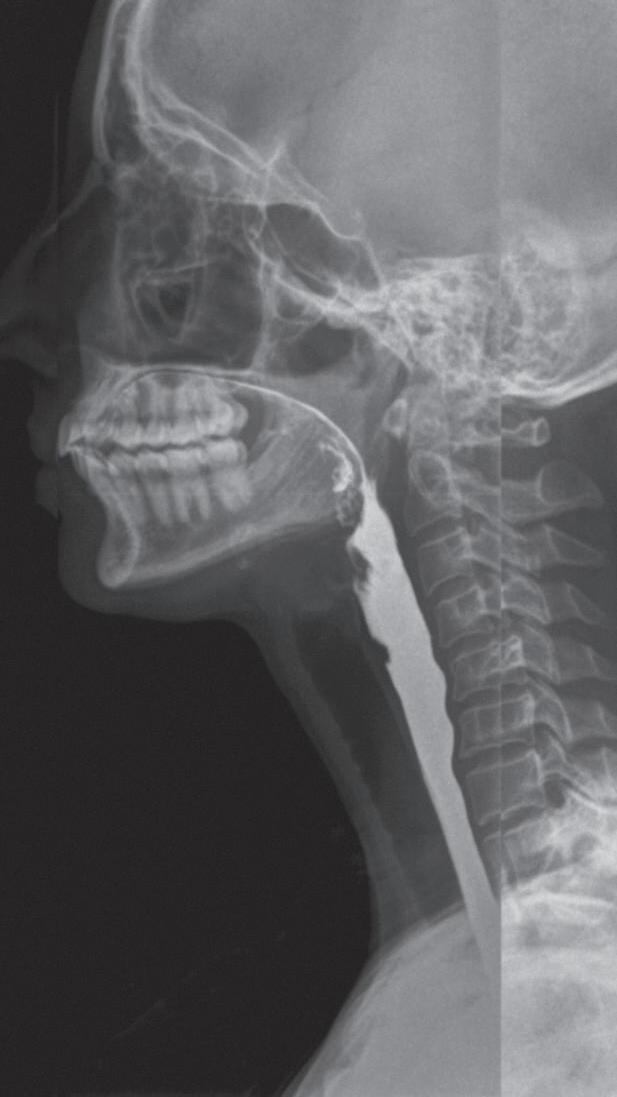

Fig. 1-1. Montagem de duas imagens radiográficas em visão anteroposterior demonstrando o percurso da deglutição desde a cavidade oral até o estômago (a) no adulto e (b) no bebê.

Fig. 1-2. Demonstração das estruturas envolvidas no processo da deglutição nas visões (a) lateral e (b) anteroposterior na imagem radiográfica.